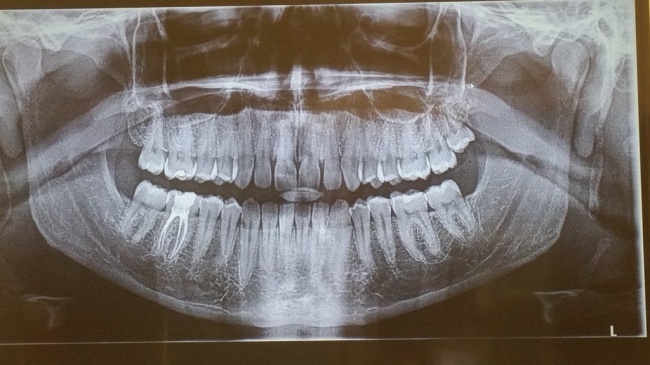

14. Відсутність зубів мудрості

20 % людей народжується без зубів мудрості, це вважається варіантом норми. У якихось країнах таке явище зустрічається частіше, а в якихось-рідше. Наприклад, відсутність зубів мудрості помічено майже у 100 % корінних народів Мексики, чого практично не буває у тасманийцев. Така різниця пов'язана з геном PAX9 і, швидше за все, з рядом інших генів.